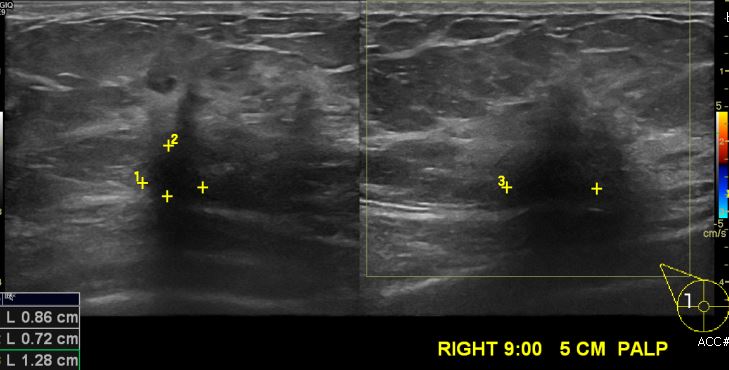

우측 유방에 만져지는 멍우리로 내원하신 60대 여성분으로 우측 9시 방향에서 5cm 떨어진 거리의 만져지는 멍우리 조직검사 시행하여 우측 침윤성 유관암 진단 되었습니다.